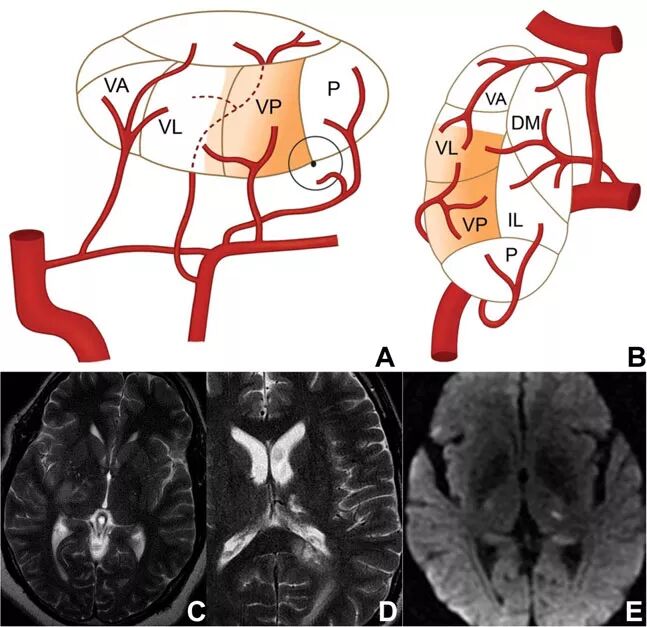

该部位由脉络膜后动脉供血。脉络膜后动脉也来自PCA的P2段,同样是一组小血管组成。目前关于该部位梗死的报道数量仍然有限,在已有的报道中,最常见的症状为象限盲,可能伴有偏身感觉丧失,也可能存在皮质性失语和记忆障碍。

脉络膜后动脉梗死的一项特征性表现为

图8 脉络膜后动脉供血示意图和梗死影像学表现